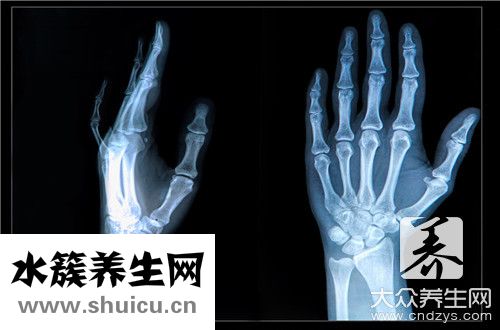

(0)那是身体手腕周边的骨头,是敏感的骨头,在大家的生活中很容易发生0 )骨折这种状况。 如果发生左手舟骨骨折这样的情况,对身体的影响非常大,另外左手舟骨骨折的治疗也不方便,所以需要特别重视,下面我们来详细调查一下左手舟骨骨折怎么样治疗。

1,手舟骨骨折很容易坏死,这个是手舟骨骨折最不便的地区!务必管形石膏固定最少8个周乃至更久!2,手舟骨骨折断端一般 无挪动,可是血液循环系统十分受到限制,因此 随时随地观查是不是坏死,一但坏死马上手术治疗切除!3,石膏固定期内,坚持不懈康复训练!管形熟石膏由于是密闭式的,里边免不了瘙痒,请别用东西塞进去抓,防止抓烂感染,用乙醇侵润就可以了!

有关手舟骨折的医治标准 :1)异常手舟骨骨折而X线片末见骨折线者,先要按骨折开展固定不动,2星期过后线片复诊,如果没有骨折,已不固定不动,若有骨折,则应再次连续固定不动,直到骨折愈合;(2)无挪动骨折者,能用无垫片短臂管形石膏固定上臂旋前,腕背伸30°桡偏,及大拇指对掌位6~8周或更长期;

(3)有挪动骨折或陈旧性骨折行得通桡骨茎突摘除,内固定不动或植骨术术,石膏固定至痊愈;(4)骨折不愈合或脑缺血坏死,行得通血管种植,或手舟骨摘除,或行肘关节结合